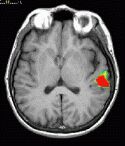

T1 weighted MRI

Transverse image at the level of the planum temporale. The left hemisphere is seen in the right side (radiological convention). The subject's task was listening to a story.The red bubble seen on the left side corresponds to areas related to complex semantic processing.